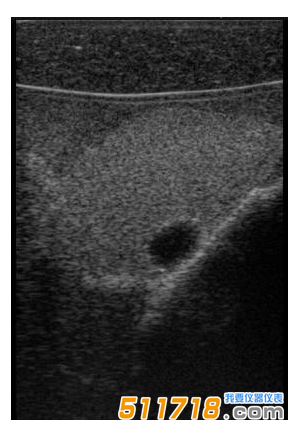

CIRS 074甲狀腺超聲訓練模體包含一個略微擴大的甲狀腺,位于一個擬人化的頸部。下巴和鎖骨被提供作為外部解剖標志。體模提供氣管,頸內靜脈和頸總動脈作為內部解剖標志。每個甲狀腺葉包含一個囊腫和一個等回聲僵硬病變??梢栽诩谞钕賰榷ㄖ粕a各種結節。*有材料都配制成超現實的。

略微擴大的甲狀腺包含單個囊腫和每個葉中的一個等回聲,僵硬的病變。

可以對每個囊腫進行細針抽吸。每個僵硬病變都設計用于超聲彈性成像的可視化,并且可以進行活組織檢查。這些病變對甲狀腺是等回聲的并且具有標準的B模式成像。

單純囊腫